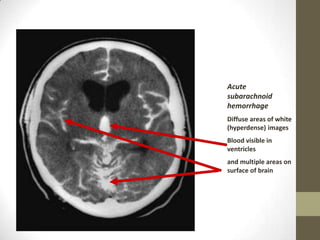

Acute subarachnoid hemorrhageDiffuse areas of white (hyperdense) imagesBlood visible in ventriclesand multiple areas on surface of brain

Acute subarachnoid hemorrhageDiffuseareas of white (hyperdense) imagesBlood visible in ventriclesand multiple areas on surface of brain